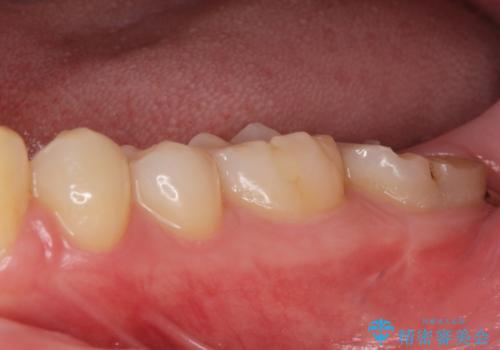

他院での治療に不信感 虫歯除去後のジルコニアクラウン

- 歯が痛くなり、他院で治療してもらったところ不信感があり、当院に受診に来られました。

神経をとる処置をされた形跡がありましたがまだ虫歯が残っていたので全て取り除き、壁を立てて根管治療ができる状態にして、根管治療・ジルコニアクラウンで治療を行いました。

- ジルコニアクラウン・仮歯 12.1万円 根管治療(イニシャル)・ファイバーコア 13.2万円費用は治療当時の料金となります